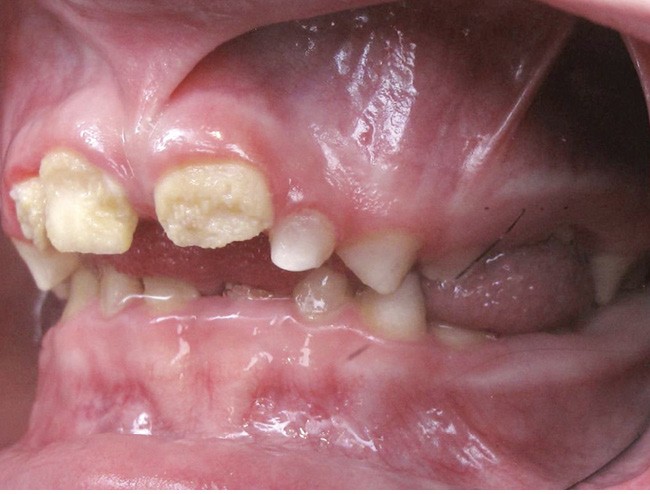

Il existe des anomalies dentaires (tabl. I) [1-12], mais aussi occlusales associées aux AI (fig. 1 et 2).

Selon de nombreuses études, l’anomalie occlusale la plus fréquemment retrouvée en association avec les AI est l’infraclusion antérieure, puisqu’elle est retrouvée chez 22 à 64 % des patients présentant cette affection, et encore plus chez les femmes [2,8,13-19]. Cette anomalie touche tous les types d’AI mais à des degrés très divers. Son incidence semble élevée dans les formes hypominéralisées, moindre dans les formes hypoplasiques et nettement moindre dans les formes hypomatures [8,17,18]. La sévérité de l’atteinte amélaire ne semble pas corrélée avec la présence ou l’intensité de cette malocclusion [17].